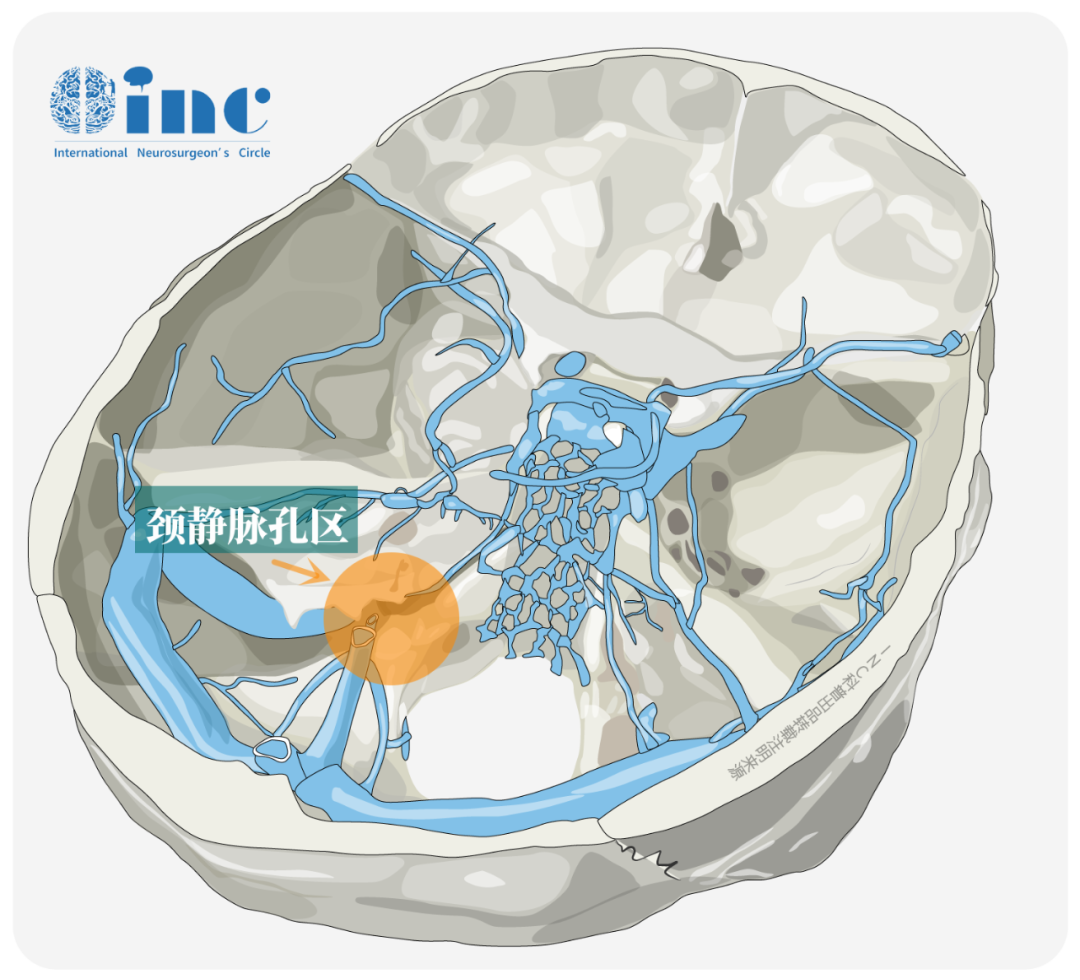

声音嘶哑、饮水呛咳、吞咽困难等症状可能与颅底颈静脉孔区病变相关。颈静脉孔区作为神经外科高难度手术区域,其解剖特点包括位置深在、周围结构复杂、个体形态差异大,且内有重要神经血管通过。

颈静脉孔主要通行三支重要神经:司咽喉感觉与运动的舌咽神经(CN IX)、调控心跳及内脏功能的迷走神经(CN X),以及控制耸肩、转头动作的副神经(CN XI)。同时颅内血液经颈静脉球在此处汇入颈内静脉。该区域发生肿瘤时易压迫这些神经血管,引发声音嘶哑、饮水呛咳、吞咽困难和搏动性耳鸣等症状复合体。